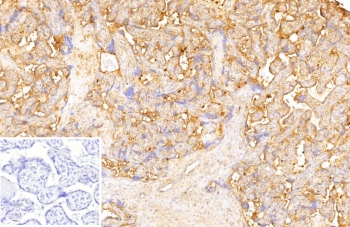

Immunohistochemistry of DR3 Ligand antibody in human placenta tissue. FFPE human placenta shows strong membranous and cytoplasmic HRP-DAB brown staining within trophoblastic epithelial cells lining chorionic villi, consistent with TNFRSF25 ligand / TNFSF15 expression in placental and endothelial-associated compartments. Clone VEGI/13117 was used as a monoclonal antibody for detection. An inset image shows PBS substituted for the primary antibody as a negative control, demonstrating absence of specific staining. Heat-induced epitope retrieval was performed by heating sections in 10 mM Tris with 1 mM EDTA, pH 9.0, for 45 minutes at 95oC followed by cooling at room temperature for 20 minutes prior to staining.